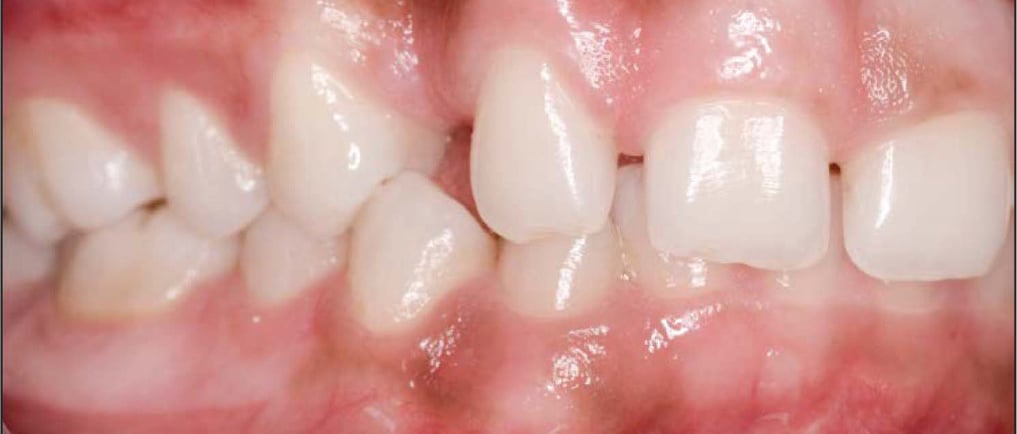

Impacted maxillary canines—where the upper canine teeth fail to erupt properly—are a challenging issue for orthodontists, affecting roughly 1-2% of the population. These teeth play a crucial role in your bite and aesthetics, but when they remain impacted, they can cause crowding, misalignment, and damage to adjacent teeth. While traditional braces have been the standard treatment, clear aligners are now gaining popularity as a more discreet and comfortable option. However, treating impacted canines with aligners comes with specific challenges that require careful management.

Impacted maxillary canines are difficult to treat because of their deep position in the jaw and the need for precise forces to move them into place. For treatment to succeed, the canine must be guided slowly along its eruption path while creating enough space for it in the dental arch. Traditionally, braces with their ability to exert stronger and more controlled forces have been preferred. However, advancements in aligner technology are making clear aligners a viable option, especially for patients who prioritize aesthetics.